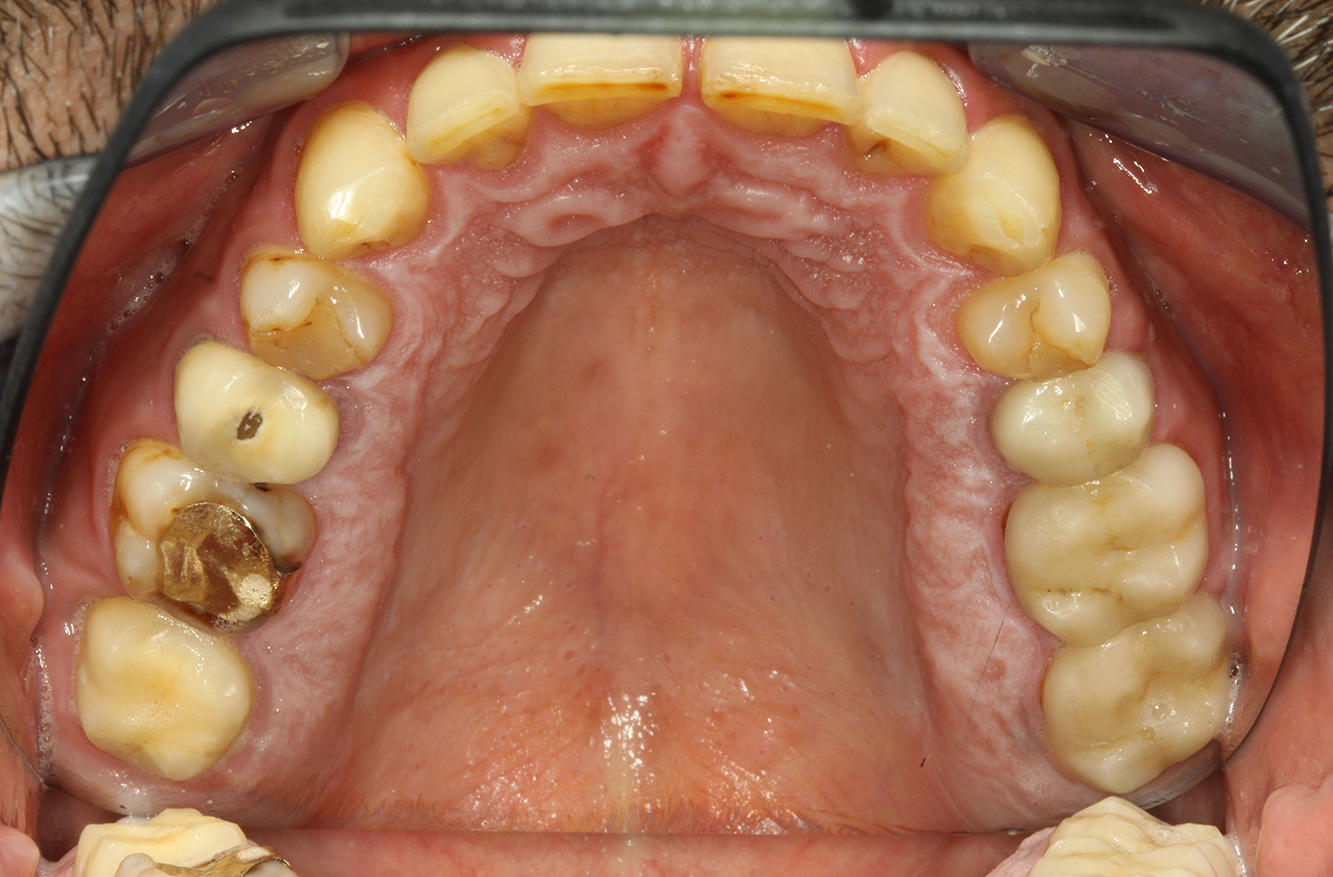

Der Patient ist 39 Jahre mit Z.n. Herzklappenersatz wegen Klappenfehlers und Endokarditis. Als Antikoagulans (Gerinnungshemmer) wird regelmäßig ASS 100 eingenommen. Aus dem Bereich Lebensstil ist die Ernährungsweise als kariesfördernd einzustufen, da mit hoher Regelmäßigkeit zuckerhaltige Lebensmittel sowie sechs bis sieben Mahlzeiten täglich verzehrt werden. Die Mundgesundheit des Patienten zeigt ein mittleres Kariesrisiko mit aktiven Läsionen. Das Parodontitisrisiko ist niedrig, es besteht eine Gingivitis. Es ergeben sich folgende Empfehlungen für die Prophylaxebehandlung.